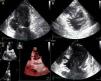

The patient was admitted with a diagnosis of non-ST-elevation myocardial infarction. Cardiac catheterization performed to exclude coronary disease identified myocardial bridging at various points along the left coronary artery (mid anterior descending, septal branches and distal branches of the first diagonal), as well as several left and right coronary artery-left ventricular fistulae. A recanalized thrombus was observed in the posterolateral branch. Two-dimensional transthoracic echocardiography showed asymmetric LV hypertrophy mainly involving the ventricular septum (22 mm) and lateral walls and a basal posteroinferior aneurysm. Global systolic function was preserved (∼55% by Simpson's biplane method). Two intramyocardial recesses were observed in the basal part of the inferoseptal wall communicating with the LV cavity, around 4 mm in diameter, the larger one traversing almost the entire thickness of the wall but with no interventricular communication. The left atrium was severely dilated and spontaneous contrast was seen in the left chambers.

Transthoracic echocardiography showing (A) basal posteroinferior aneurysm (two-dimensional apical 2-chamber view); (B) endomyocardial trabeculations and recesses communicating with the ventricular cavity (two-dimensional parasternal short-axis view); (C and D) two intramyocardial recesses in the basal portion of the inferoseptal wall communicating with the left ventricular cavity, around 4 mm in diameter, the larger one traversing almost the entire thickness of the wall but with no interventricular communication (two- and three-dimensional images, respectively, apical 4-chamber view).